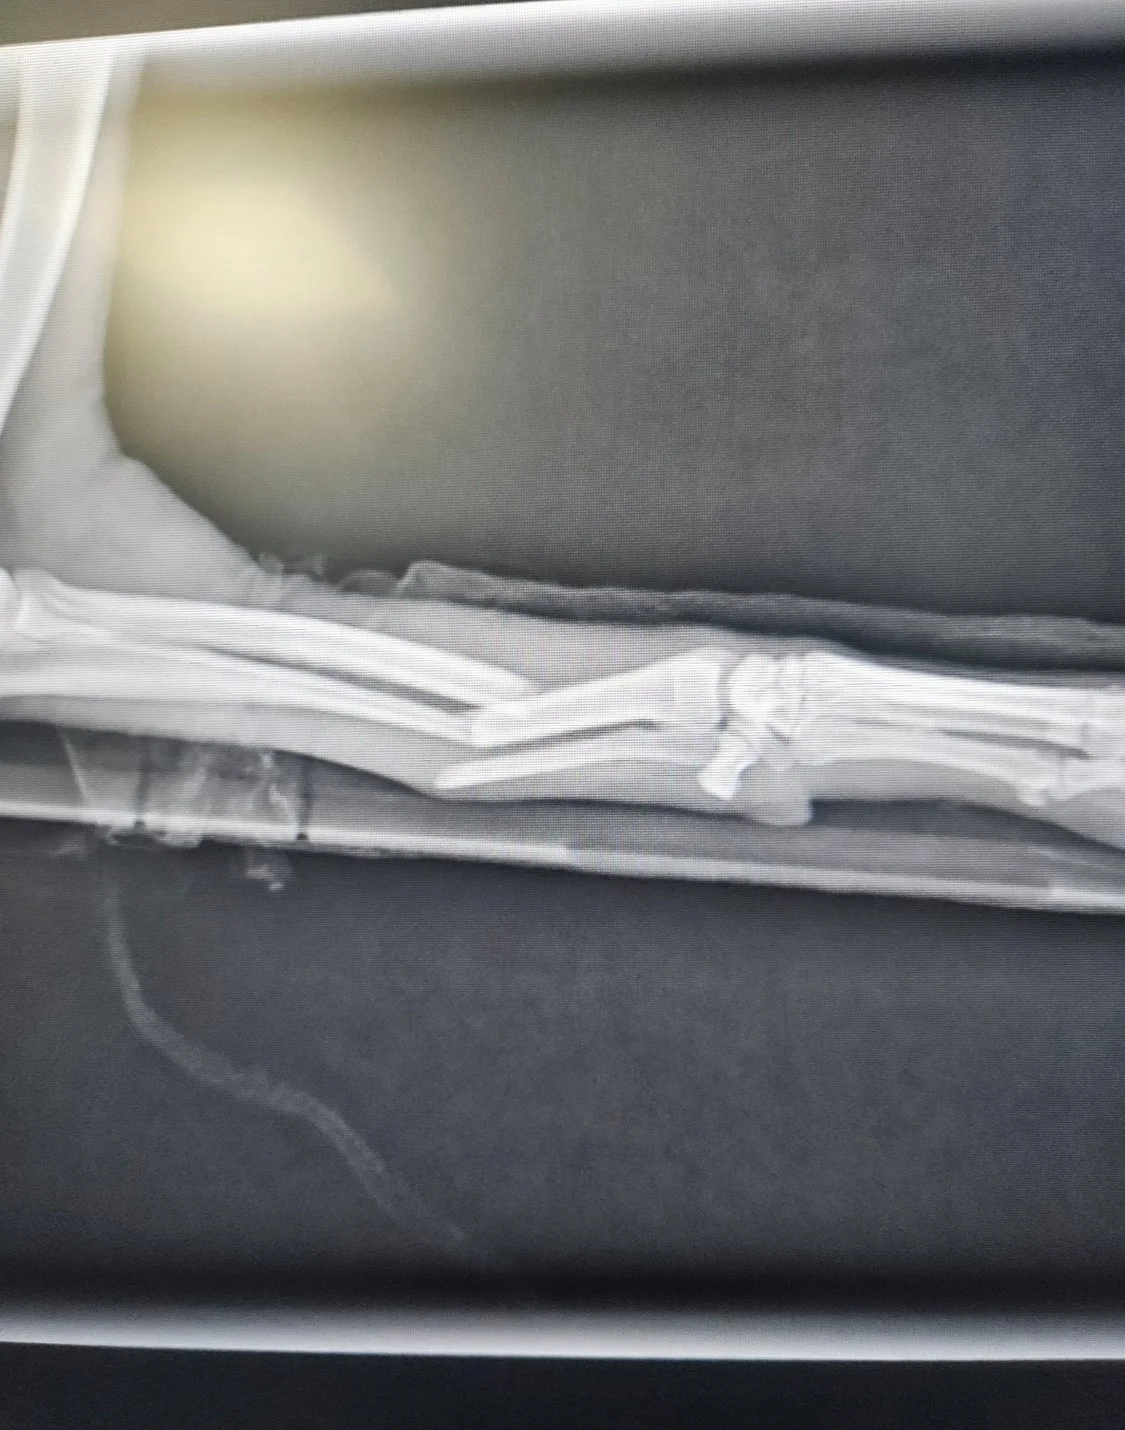

The devastation was immediate, suffering a serious fracture of his radius and ulna.

Teaming up with the kind-hearted samaritan, and Tater's generous friends and family, we were able to rally enough funds in just a few days for his leg saving procedure - despite some calcification, his bones were able to be re-broken and re-aligned without the use of a plate & pins - allowing Tater to continue to thrive on his three unstoppable legs.